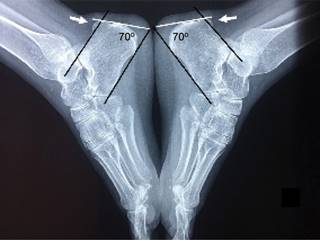

Figura 2: Radiografías laterales de ambos pies, el ángulo de Fowler (normal entre 44 y 70o) se define por la intersección de una línea tangencial a la prominencia posterosuperior de la proyección de la bolsa y otra línea tangencial al tubérculo anterior y la tuberosidad medial. Las líneas paralelas se definen por la tangente basal al tubérculo anterior y la tuberosidad medial y una línea paralela desde el labio posterior de la faceta articular talar. Cuando la tuberosidad posterosuperior supera la línea superior se puede considerar deformidad de Haglund.